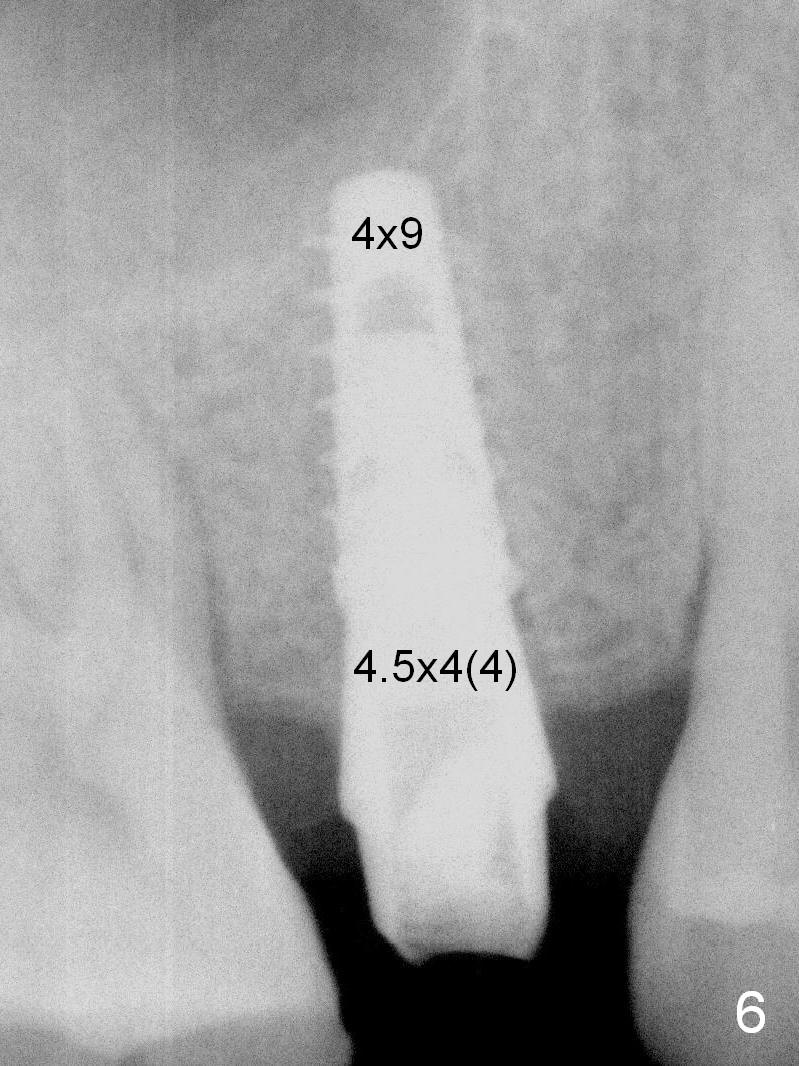

A 47-year-old man returns emergently with subgingival fracture of the lingual (L) cusp of the tooth #4 (Fig.1-3). After extraction (no bony defect) without drilling, a 4x11 mm dummy implant is placed as a tap drill with satisfactory stability (Fig.4,5). To get subcrestal placement, a shorter (4x9 mm) implant is inserted with insertion torque of < 35 Ncm. In retrospect, a larger implant (4.5 mm) would be better in term of primary stability. After allograft placement into the buccal and lingual gaps, a 4.5x4(4) mm abutment is placed for an immediate provisional. There is a peri-implant gap 7 months postop (Fig.7<, as compared to the implant at #2 (6 months postop)) . When the loose abutment is being retightened, the patient feels pain, although the gingiva appears healthy (Fig.8). A larger implant should have been used; the abutment should have been removed. The implant dislodges while the abutment is untightened 8 months postop. The osteotomy is found intact. A 4.5x11 mm dummy implant is placed 2 mm subgingival with 20 Ncm (Fig.9). When a 4.5x11 mm definitive implant is placed 3 mm subgingival (Fig.10,11), torque reaches 50 Ncm. A 5.5x3 mm healing abutment is placed. Three months postop, the implant is stable (Fig.12,13) and impression is taken.